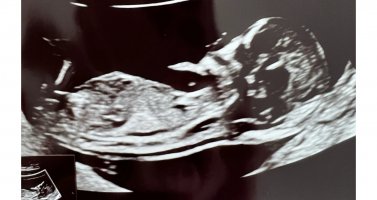

Det var i slik vinkel som bilde nr 2 her at min GY også gjetta på jente 12+3Synes ikke så godt her.. målt til 12+2 men gyn hadde en anelse ved bilde 2 der![]()

hu såg aldri etter "nub".